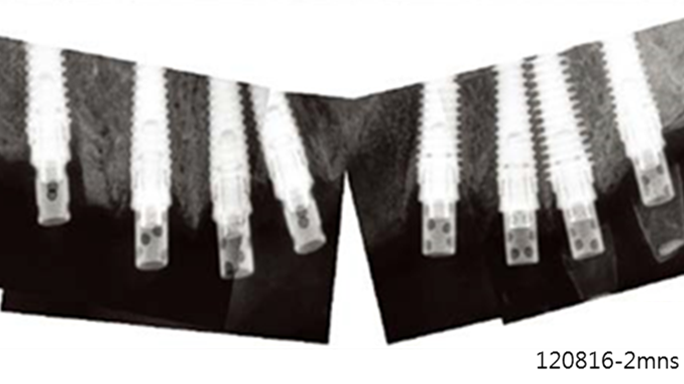

Clinical case: Extraction of all teeth in upper maxilla,

immediate implant placement, & provisionalization

- Courtesy of Dr. Iulian Filipov, Romania -

Keywords

AnyRidge, immediate placement, immediate provisionalization, maxillary fully edentulous case, initial stability, edentulous, Dr. Iulian Filipov, R2GATE, MEGA ISQ

Products:

AnyRidge implant system, Mega ISQ, R2GATE

“AnyRidge ensures long-term biological stability

& functionality even in

full-mouth rehabilitation case. ”